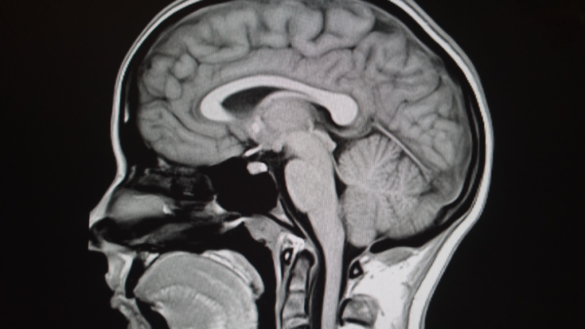

Trods mange undersøgelser og forskning, har man ikke klarlagt årsagen til autisme. Hvordan hjernen udvikler sig, og bearbejder informationer fra omgivelserne påvirkes af vores gener. Autisme, der viser sig som begrænsninger i adfærd, må derfor formodes at være forårsaget af biologiske og genetiske faktorer.